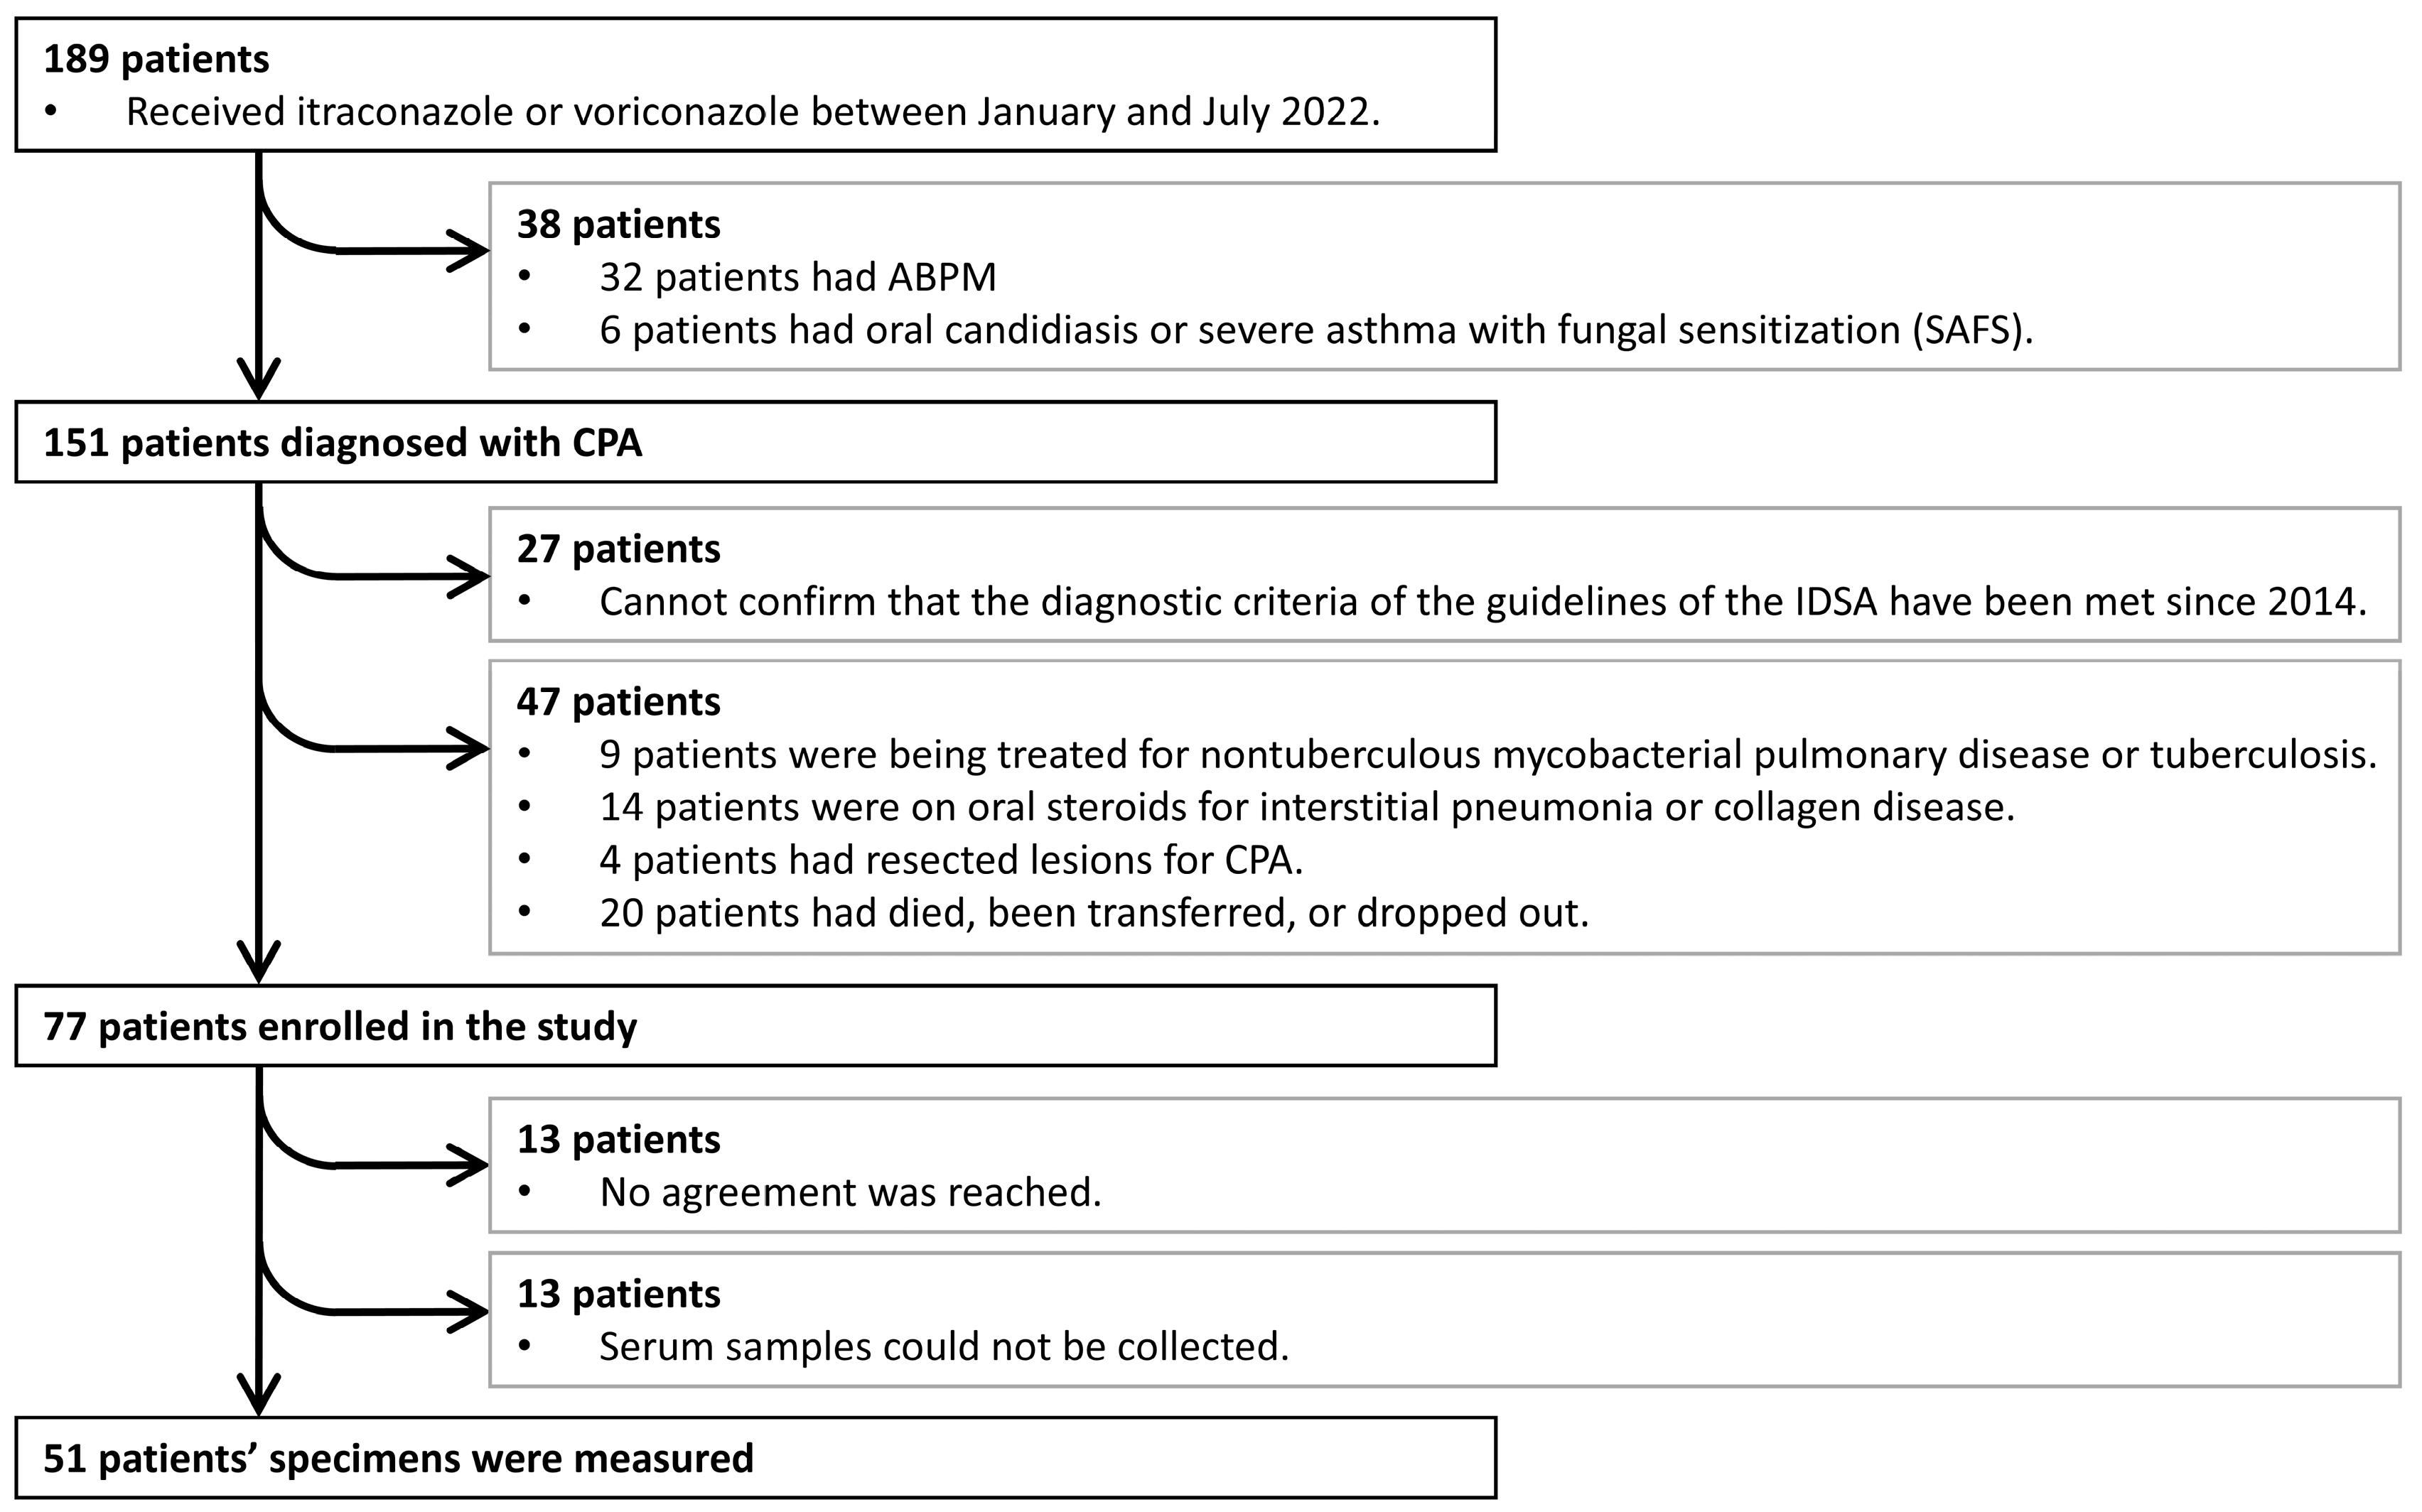

2. Materials and Methods

2.1. Patient Characteristics